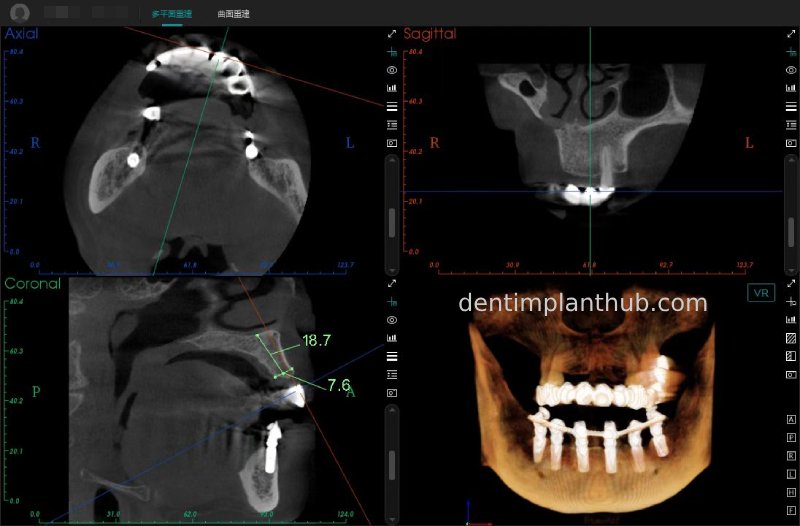

Maxillary condition as shown by CBCT on 13/5/24

16

14

12

22

24

26

Details of implant sites, protocols, implant types, composite abutments, 13.5.24

16, implant model 4810, requires an internal elevation of the maxillary sinus floor and an RC series straight composite abutment;

14, implant model 4812, requires an RC series 15° composite abutment;

12, implant model 4112, requires an RC series 30° composite abutment;

22, implant model 4112, requires an RC series 30° composite abutment;

24, implant model 4812, requiring an RC Series 15° composite abutment;

26, implant model 4810, requiring an internal maxillary sinus floor lift, requiring an RC Series straight composite abutment;